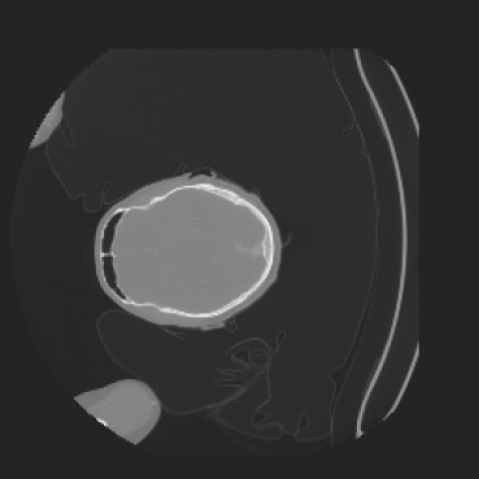

As shown in Figure 5, the generated slices exhibit high consistency across adjacent slices. The anatomical structures and semantic patterns are smoothly and coherently preserved between slices, indicating that our model is capable of generating 3D-consistent synthetic images rather than isolated 2D slices.

To demonstrate the advantages of 3D semantic image synthesis over 2D semantic semantic image synthesis, we conducted a detailed comparison with the SegGuidedDiff [26] model. SegGuidedDiff generates medical images based on 2D semantic maps, producing individual 2D slices that are later stacked to form a 3D image. However, this approach has limitations in capturing spatial continuity and coherence across slices, which is critical for representing the spatial structure of 3D medical images. As a result, inconsistencies often arise between different slices, particularly in preserving anatomical structures across the coronal and sagittal planes. The generated images exhibit varying levels of denoising, resulting in differences in brightness and sharpness across the images. This inconsistency in denoising can lead to noticeable variations in visual quality, where some regions appear clearer and others less distinct.

The motivation for this work arises from the need to address these limitations in the synthesis of 3D medical images. Current techniques do not produce high-resolution 3D images that preserve spatial coherence and capture the full complexity of medical data, as shown in Figure 2, 5. The development of advanced 3D generative models tailored specifically for medical imaging could not only improve the quality of synthetic medical images but also help alleviate data scarcity, enhance privacy protection, reduce computational requirement and ultimately advance the use of deep learning in healthcare applications.